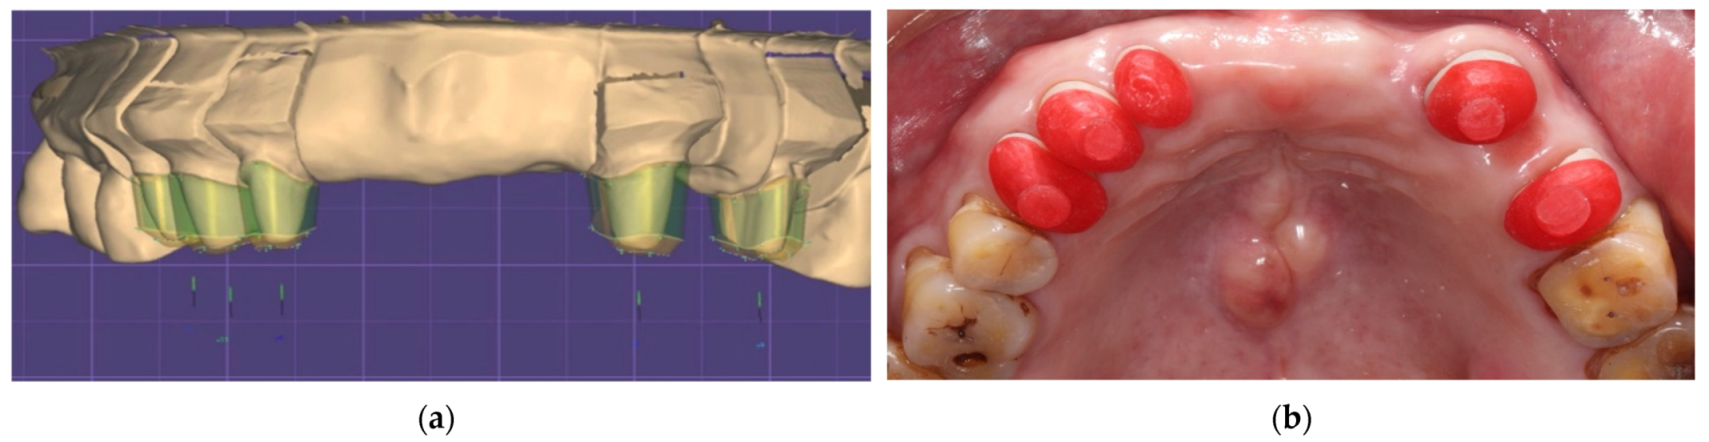

2. Case Description